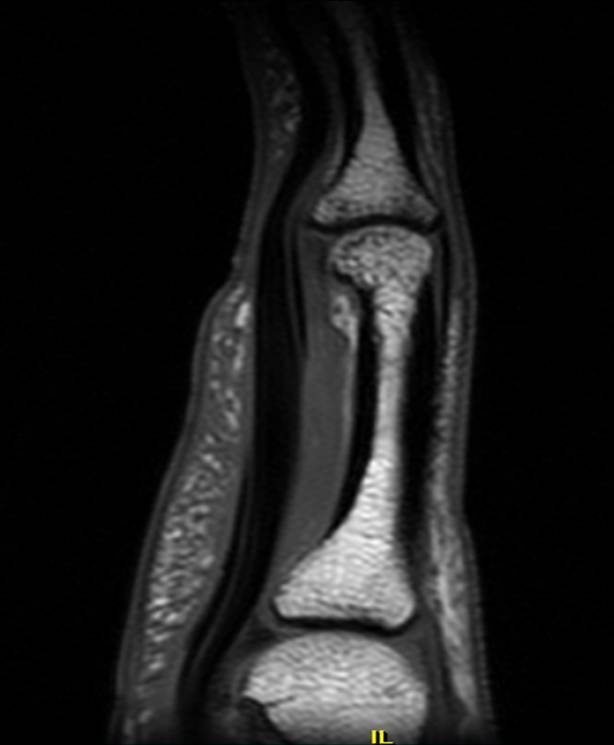

A2 pulley injury ring finger Image Torn A2 Pulley  For a2 and a4 injuries, typically greater than 2 mm of distance is considered pathologic.   an injury to the a2 pulley could be as simple as a mild strain, or as advanced as a complete rupture of the pulley. Most commonly, either the middle or index digit is the injured finger. Pain on the palm side of finger and. Torn A2 Pulley.

Finger A2 pulley injury Image Torn A2 Pulley  Pain on the palm side of finger and tenderness with pressure. Hearing a pop at the time of the injury. Measuring the distance of bowstringing of the flexor tendons from the bone using ultrasound. A4 is the most flexible.  how do you diagnose and classify pull the injuries?  the most common injury in climbers is the a2 pulley. Torn A2 Pulley.

Finger pulley injury Radiology Reference Article Torn A2 Pulley  A4 rupture often seen with a3 rupture.  the most common injury in climbers is the a2 pulley sprain or rupture and is caused by overloading the tissue.  how do you diagnose and classify pull the injuries? Measuring the distance of bowstringing of the flexor tendons from the bone using ultrasound. Pain on the palm side of finger and. Torn A2 Pulley.

A2 pulley injury ring finger Image Torn A2 Pulley    the most common signs of finger pulley injuries include: Accurate diagnosis is necessary to identify.  the most common injury in climbers is the a2 pulley sprain or rupture and is caused by overloading the tissue. Most commonly, either the middle or index digit is the injured finger. A4 rupture often seen with a3 rupture. For a2 and a4. Torn A2 Pulley.